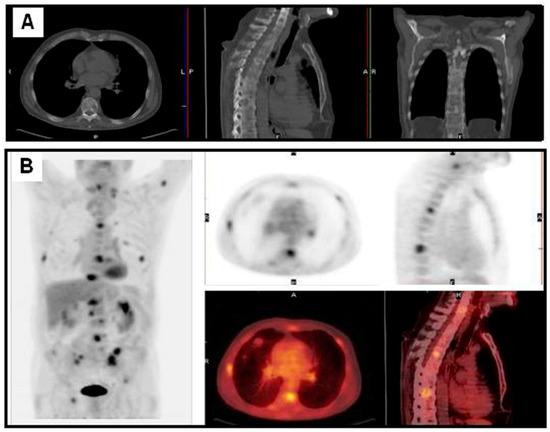

Figure 4.

Patient with a NSCLC in the left superior lobe treated three years before with chemo-radiotherapy. A radiological exam showed sclerotic bone lesions (A); FDG PET/CT showed multiple bone, left supraclavicular lymph nodes and lung metastases (B).